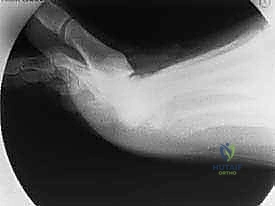

- التصوير بالأشعة السينية (X-rays): تُجرى الأشعة في وضعية الوقوف (تحميل الوزن) لرؤية المفصل في حالته الوظيفية. تظهر الأشعة بوضوح حجم النتوءات العظمية، ومدى تضيق المساحة المفصلية نتيجة تآكل الغضروف.

تُعد جراحة "استئصال النتوء العظمي الظهري" الإجراء الجراحي الأكثر شيوعاً ونجاحاً لعلاج تصلب إبهام القدم في مراحله المتوسطة (الدرجة 1 و 2، وبعض حالات الدرجة 3). كلمة "Cheilectomy" مشتقة من اليونانية، وتعني "إزالة الشفة"، في إشارة إلى إزالة الحافة أو النتوء العظمي الزائد.

- استئصال النتوء العظمي: باستخدام أدوات جراحية دقيقة جداً (مثل المنشار الجراحي الدقيق أو الأزاميل الخاصة)، يقوم الدكتور هطيف بإزالة النتوء العظمي الظهري. يتم عادةً إزالة حوالي 25% إلى 30% من الجزء العلوي للعظمة المشطية الأولى.

- اختبار الحركة أثناء الجراحة: قبل إغلاق الجرح، يقوم الدكتور هطيف بثني إصبع القدم يدوياً للتأكد من استعادة نطاق الحركة المطلوب (عادة 60 درجة على الأقل) والتأكد من عدم وجود أي عوائق ميكانيكية متبقية.